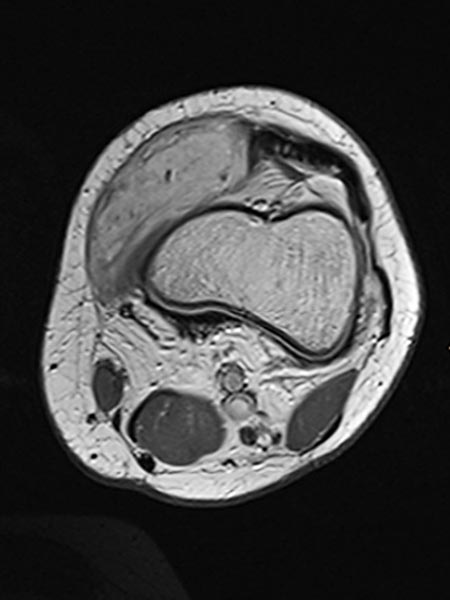

Axial T2-weighted MRI shows a hyperintense, homogeneous mass in the area of the swelling. Morphology very compatible with a venous malformation. Strikingly, some smaller central flow voids suggestive of arteries in the lesion.

The axial T2-weighted, fat-saturated MRI slightly more cranial again depicts typical signs of a venous malformation with severe hyperintensity of the lesion.